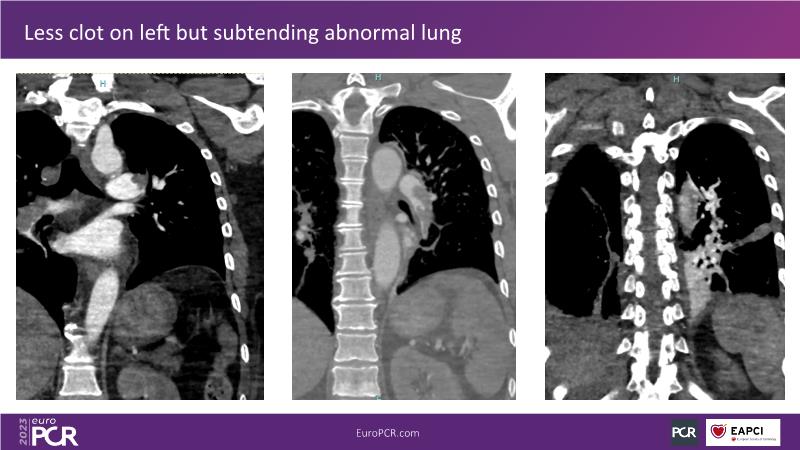

Primary percutaneous pulmonary intervention (pPPI) of acute pulmonary embolism with computer-aided mechanical aspiration

- To share practical experiences from real case scenarios